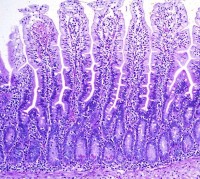

La Enfermedad Celíaca o enteropatía sensible al gluten (Trigo, Avena, Cebada, Centeno) se asocia a una inflamación crónica del intestino delgado en el hombre y se caracteriza por una atrofia de las vellosidades intestinales e interferncia en la absorción de nutrientes. Una de las pocas razas en las que se ha visto algunos ejemplares afectados por éste mal o mayor frecuencia de padecerlo es el Setter Irlandés, aunque también se ha visto en otras razas y en perros cruza.